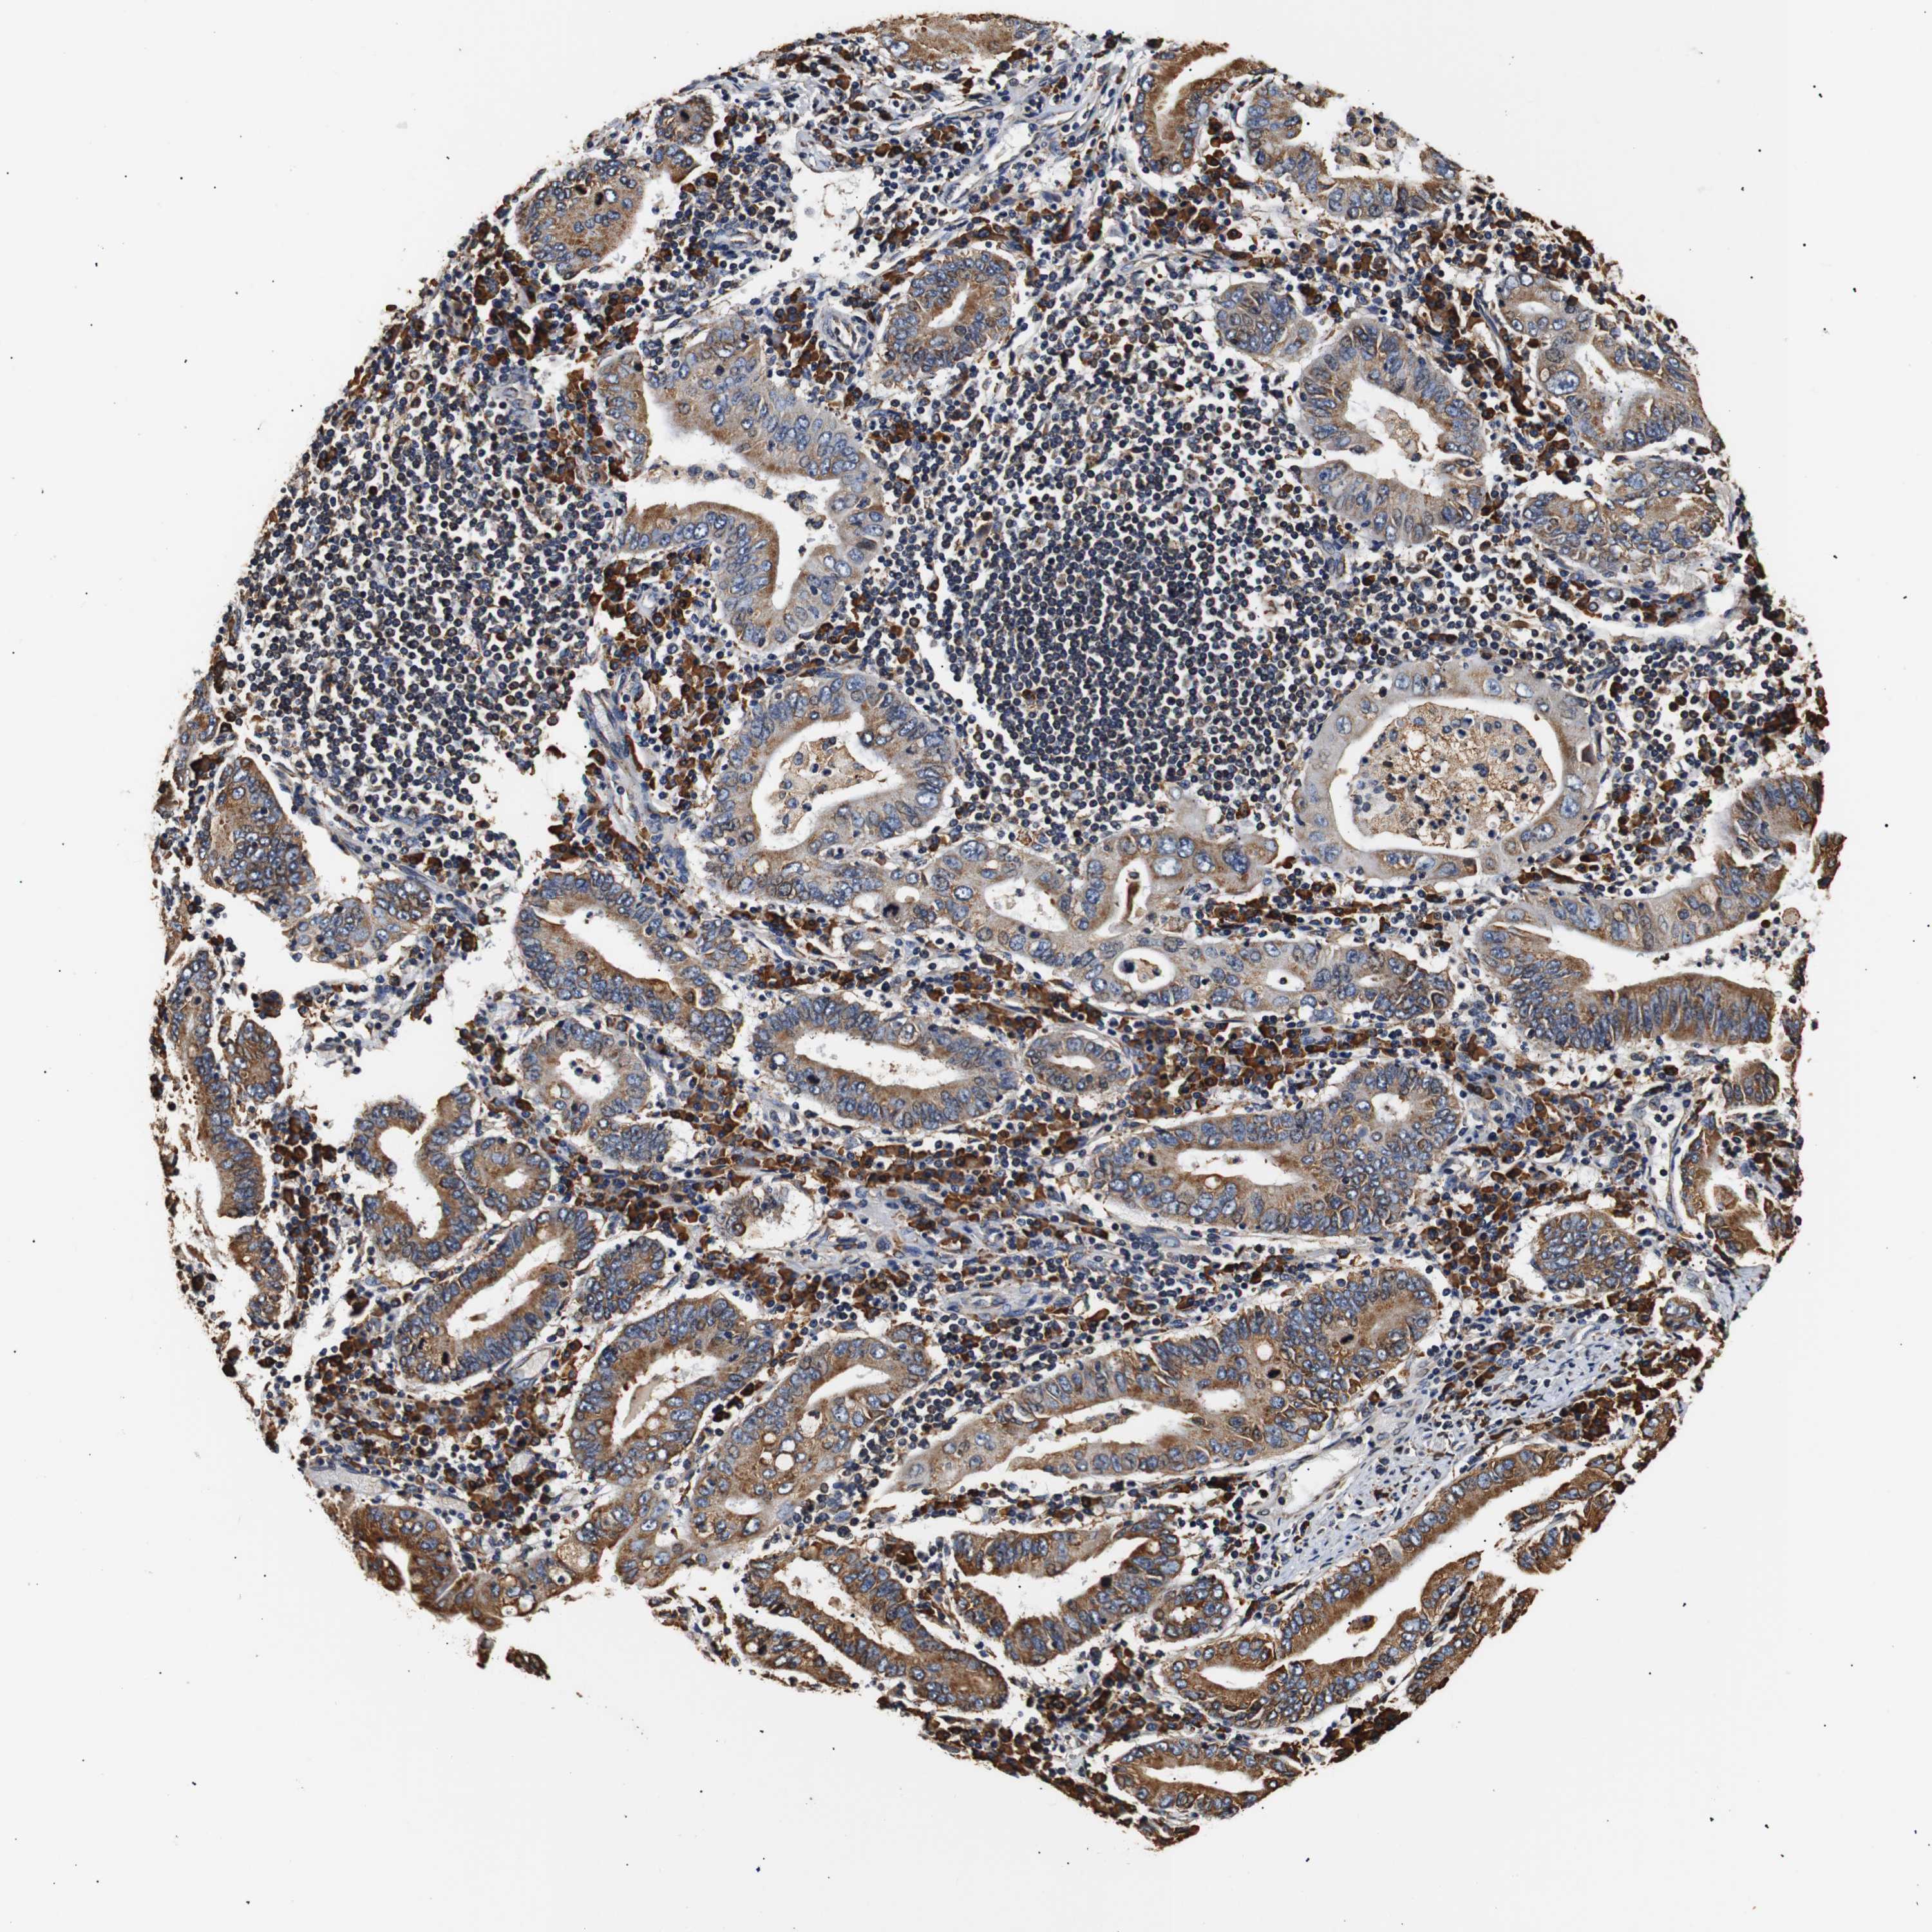

STOMACH CANCER - Protein expressioni

A mouse-over function shows sample information and annotation data. Click on an image to view it in a full screen mode. Samples can be filtered based on level of antibody staining by selecting one or several of the following categories: high, medium, low and not detected. The assay and annotation is described here.

Note that samples used for immunohistochemistry by the Human Protein Atlas do not correspond to samples in the TCGA dataset.

Antibody stainingi

Antibody staining in the annotated cell types in the current human tissue is reported as not detected, low, medium, or high, based on conventional immunohistochemistry profiling in selected tissues. This score is based on the combination of the staining intensity and fraction of stained cells.

Each image is clickable and will lead to virtual microscopy that enables deeper exploration of all samples and also displays staining intensity scores, fraction scores and subcellular localization as well as patient and tissue information for each sample.

Antibody HPA012616

Staining

High

Medium

Low

Not detected

Intensity

Strong

Moderate

Weak

Negative

Quantity

>75%

75%-25%

<25%

None

Location

Nuclear

Cytoplasmic/membranous

Cytoplasmic/membranous,nuclear

Adenocarcinoma, NOS

Adenocarcinoma, High grade